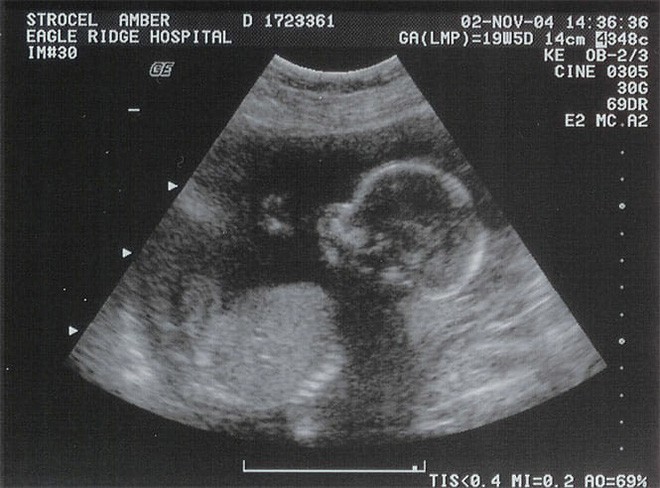

Khoảng 21 tuần sau khi mang thai, Briony đến bệnh viện để khám thai định kỳ. Bác sĩ siêu âm và thông báo cô đang mang bầu một bé gái. Thế nhưng, niềm vui của hai vợ chồng Briony kéo dài chẳng được bao lâu thì chỉ vài tuần sau chuyến thăm khám đó, họ đã phải nhận cú sốc không nói nên lời.

Khi đi siêu âm chị Briony mới nhận tin sốc.

Khi Briony và Mike đến bệnh viện, các bác sĩ ngay lập tức siêu âm để xem tại sao đứa trẻ không di chuyển trong bụng mẹ và nguyên nhân là thai đã ngừng phát triển từ tuần thứ 22. Bác sĩ cho rằng đây là trường hợp khá hiếm.